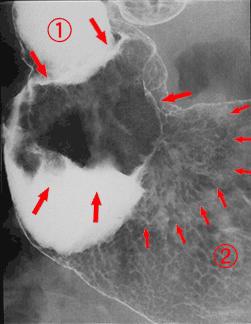

clasificación del pacienteTumor Epitelial Maligno/Adenocarcinoma

parte(separada por órganos)estómago(región)/antro

método de exámenRayos X

clasificación ectoscópica de tumoresTipo 1(Tipo protuído)/

diámetro mayor del tumor40 -

grado de penetraciónmp

múltiples tumores(en un mismo órgano)presente(simultáneo)